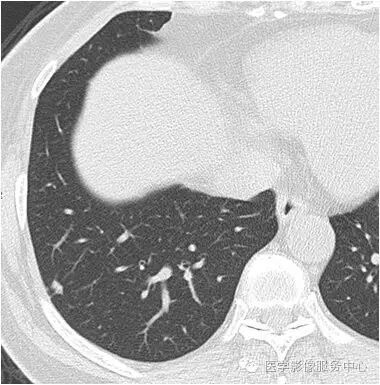

影像图片

结果:肺内淋巴结

黄勇主任解读:肺内淋巴结以老年人和吸烟者多见。

影像上常见于胸膜或叶间胸膜下,迄今为止,所有的报道均距胸膜或叶间胸膜小于2.0cm。也可以表现为与胸膜或叶间胸膜相贴的结节。绝大多数位于中下叶(气管隆突水平以下),上叶也可见到,但较少见。

长径均小于12mm。典型的形状为三角形,也可以为梭形、圆形或椭圆形。诊断的关键在于见到1-5条细线与胸膜、叶间胸膜相连,或注入肺静脉,但厚层CT显示欠佳。有作者病理对照线状影为小叶间隔,有作者病理对照为淋巴管。其实是统一的,因为淋巴管走行于小叶间隔内。

需要与小肺癌、肺转移瘤进行鉴别。肺内淋巴结除细线状影外,边缘清晰无分叶,无毛刺,是与肺癌鉴别的关键。有作者对9例胸膜下的小于1cm的肺转移瘤进行对照,后者均为圆形,且无线状影与胸膜或肺静脉相连。

对怀疑肺内淋巴结的病例,必须行薄层扫描,推荐1.5mm及以下层厚。因为在5mm层厚图像,肺内淋巴结可以由于部分容积效应表现为磨玻璃密度结节,而且对线状影及病变形状的显示也欠清晰。

诊断肺内淋巴结最关键指出在于薄层扫描见到细线状影与胸膜、叶间胸膜及肺静脉相连。